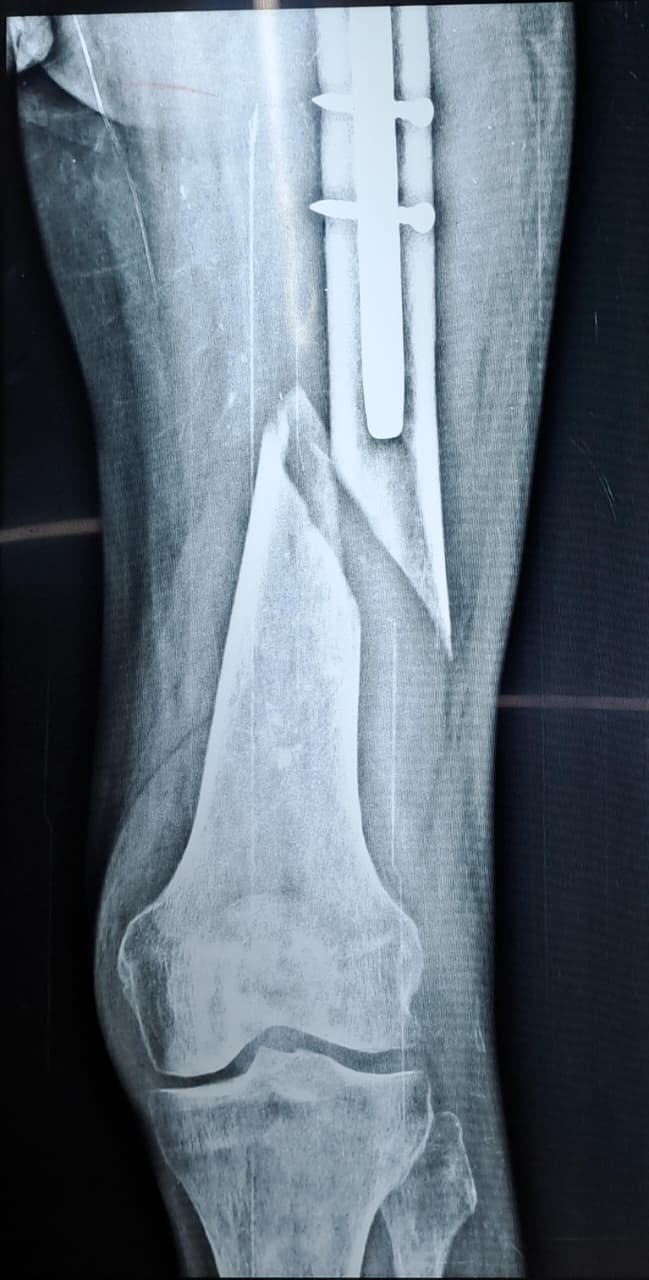

Peri-implant fracture

Open this atlas entry to review structured imaging references.

General Region 2 images 2 months ago